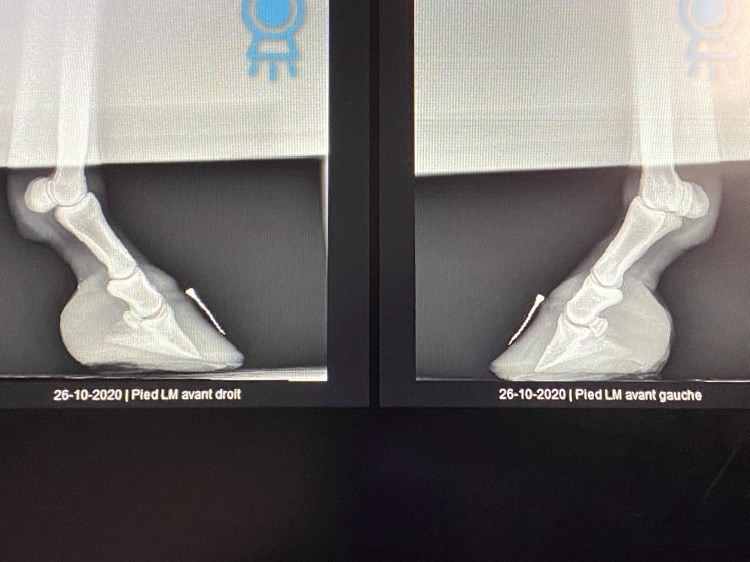

| Dire merci | Merci ! Cela voudrait dire qu'elle pourrait - plus tard- retourner à l'herbe si c'est endocrinien si je comprends bien ???? Les prises de sang ont été faites, j'attends les résultats. Et oui elle a eu des radios, elles sont ici sur la page précédente. On réaligne progressivement et elle a une alimentation avec le moins possible de sucre et d'amidons CMV (magnésium +) et pré/pro biotiques et oui tous les onglets ouverts de mon ordinateur sont sur "the laminitis site" et j'en ai même imprimé qq pages pour mon vétérinaire qui était demandeur ! Merci jaimiejay |

DéconnectéDire merci | muesli08 Au sujet des radios, oui je les ai vues. Est ce que vous pourriez poster toutes les radios et peut être obtenir de votre vétérinaire les radios sans notation écrite dessus car elles masquent une partie des radios, en particulier elles empêchent de voir clairement l'épaisseur de la sole? Certainement qu'en discutant avec Remco, il vous a précisé les points importants du parage de réalignement, dont le fait, dès le premier parage de raccourcir la pince de façon à ramener le point de bascule à sa vraie position c'est à dire juste devant la vraie ligne blanche ( pour corriger l'angle dorsal ) et de faire un chanfrein en pince et sur tout le pourtour du pied ( pour supprimer les forces de séparation exercées sur les lamelles affaiblies/la paroi du sabot par le poids du cheval et permettre à la nouvelle paroi qui pousse à partir de la bande coronaire de pousser dans le bon angle parallèle à la face dorsale de P3). Les talons doivent être abaissés pour restaurer un angle palmaire autour de 5 degrés. Je ne vois pas bien à cause des inscriptions sur la radio mais la sole ne semble pas très épaisse sous la pointe de P3; il est important que la sole se développe à cet endroit et donc les talons doivent être abaissés qu'à partir de la hauteur de la fourchette, ce qui va laisser le pied en 2 plans au niveau de sa surface solaire, le temps que la sole se développe à l'avant du pied mais ce n'est pas grave si les piesds sont bien soutenus dans des boots avec des semelles épaisses à l'intérieur. J'essaie de vous faire des tracés sur les radios pour que cela soit plus clair si vous le souhaitez et de vous envoyer des infographies sur le sujet. |

| Dire merci | bon je viens donner des nouvelles ! radios de mercredi : ![]() ![]() la rotation es déjà bien corrigée là il me reste à rétablir un point de break over parfait : surtout sur base de la punaise à l'apex qui me permettra de couper pile poil où il faut. ça repousse , lentement ne pince, plus vite en talons ce qui donne de précieuses indications : que je dois surveiller la hauteur de talons chaque semaine et les garder à hauteur de la sole en permanence. Muesli n'est plus du tout sensible sur sol souple !!! Elle garde tout de même ses chaussures et semelles en permanence : vu la poche de gaz , je dois me méfier , la laisser marcher sans soutien pourrait accentuer la bascule. je pare les prochains jours (j'attends les mark ups, j'ai bien ma petite idée, mais je ne peux me permettre d'être approximative. ) édit car j'oublie toujours de refermer les parenthèses que j'ouvre et aussi pour vous dire : regardez comme la sole s'est épaissie sous la pointe de p3 en 3 semaines !! Message édité le 06/12/20 à 19:33 |

En ligneDire merci | la sold a bien repris c’est top et la deuxième radio l’alignement est pas mal du tout tu as vraiment de quoi reprendre en talon et en pince en plus. les poches de gaz vont partir avec la reprise en pince sur tes parages c’est douloureux donc fais gaffe à bien garder le pied dans des boots . maintenant c’est surtout le pied de la première radio à travailler pour reprendre l’alignement mais c’est vraiment nettement mieux |